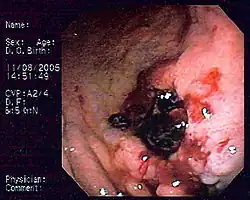

Krwawiący rak żołądka

Krwawienie związane z nowotworami może stanowić przyczynę 10–20% przypadków krwawienia do przewodu pokarmowego[76][77]. Nowotwory górnego odcinka przewodu pokarmowego wiążą się z przewlekłym krwawieniem powodującym niedokrwistość i obecność utajonej krwi w kale, a jawne krwawienie jest rzadsze[78][79]. Krwawienie mogą powodować zarówno złośliwe i niezłośliwe nowotwory nabłonkowe (rak przełyku, rak żołądka, rak dwunastnicy, rakowiak), jak i nienabłonkowe (nowotwory stromalne, mięśniakomięsak gładkokomórkowy, mięśniak gładkokomórkowy, chłoniaki, czerniak)[77][72]. Często uporczywe krwawienie jest obserwowane w przebiegu GIST, chłoniaka MALT oraz mięśniaka gładkokomórkowego[72]. Nowotwory jelita grubego, przede wszystkim rak jelita grubego, nie są źródłem istotnego krwawienia, częściej powodują ukryte przewlekłe krwawienie prowadzące do niedokrwistości z niedoboru żelaza. Jawne krwawienie z jelita grubego zwykle jest mało obfite i okresowe[80]. Jawna obecność świeżej krwi w stolcu zwana hematochezją może występować w guzach położonych w dalszej części jelita grubego, szczególnie w odbytnicy, rak w zstępnicy i esicy może powodować obecność krwi zmieszanej ze stolcem lub krwi na stolcu[81][82]. Masywne krwawienie może występować w guzach stromalnych (GIST) w jelicie grubym[83]. Również zmiany o łagodnym charakterze mogą być przyczyną krwawienia[83]. Ponadto do krwawienia z przewodu pokarmowego może dojść w niepożądanym następstwie leczenia choroby nowotworowej. Niekontrolowane nudności i wymioty związane z chemioterapią lub radioterapią mogą być powodem zespołu Mallory’ego-Weissa. Radioterapia i chemioterapia mogą powodować uszkodzenia błony śluzowej górnego odcinka przewodu pokarmowego, nadżerki i w konsekwencji krwawienie. Większość leków cytostatycznych może wywołać ostrą gastropatię krwotoczną[78]. Popromienne zapalenie odbytnicy i neutropeniczne zapalenie jelit może przebiegać pod postacią krwawienia z dolnego odcinka przewodu pokarmowego[78]. Również leki celowane o właściwościach antyangiogennych (bewacyzumab, sunitynib, sorafenib i pazopanib) oraz leki używane w leczeniu wspomagającym: niesteroidowe leki przeciwzapalne stosowane w leczeniu bólu i bisfosfoniany wykorzystywane w profilaktyce złamań patologicznych związanych z przerzutami mogą być przyczyną krwawienia do przewodu pokarmowego[77]. W wybranych programach chemioterapii lub lekach w monoterapii (terapii jednolekowej) stosuje się profilaktykę za pomocą antagonistów receptora H2 lub inhibitorów pompy protonowej[78]. Ponadto krwawienie może być następstwem zespołu rozsianego wykrzepiania wewnątrznaczyniowego lub zaburzeniem liczby oraz funkcji płytek krwi[84]. Istotna jest ocena ryzyka zakrzepowo-zatorowego i adekwatność stosowanej profilaktyki, kiedy ryzyko powikłań krwotocznych może przeważać nad korzyściami wynikającymi ze stosowania profilaktyki przeciwzakrzepowej[84].